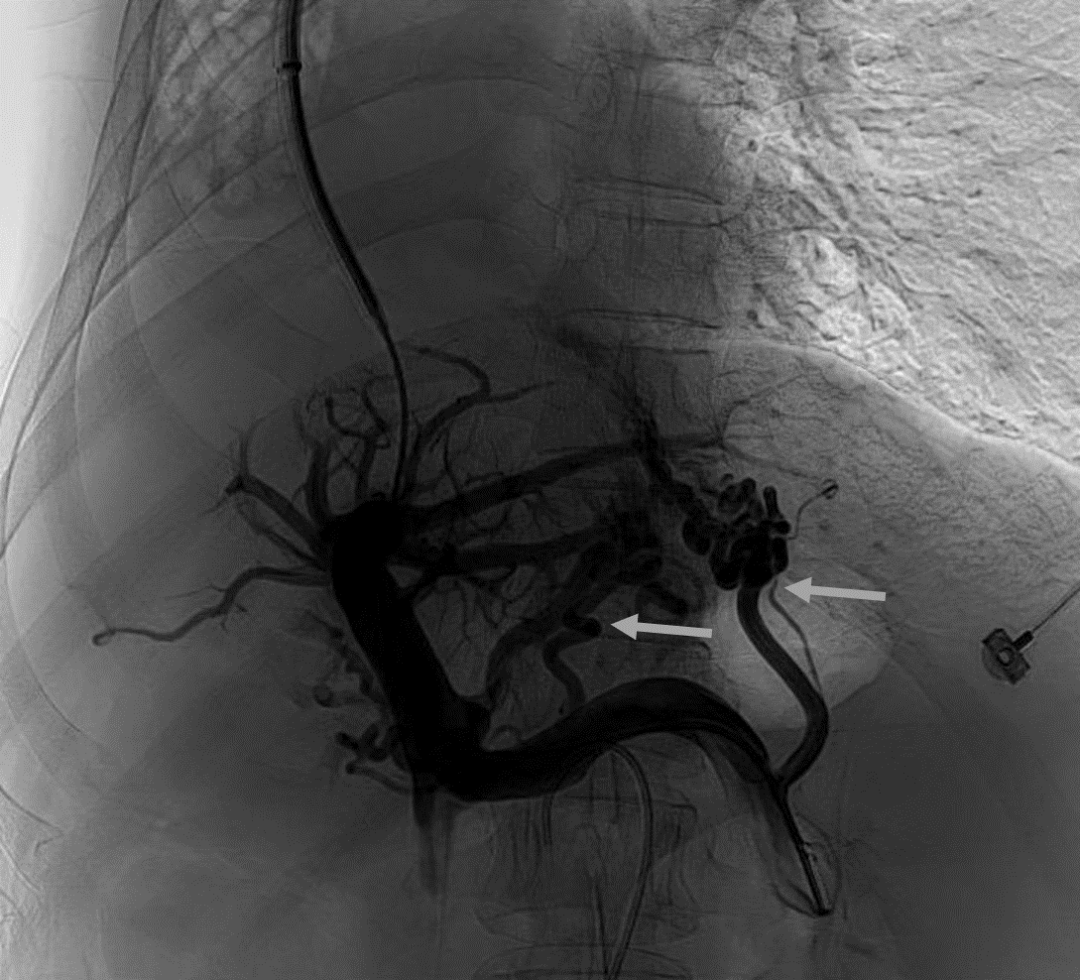

韓國宏教授介紹,TIPS手術(shù)是通過在肝靜脈與門靜脈之間的肝實質(zhì)內(nèi)建立分流通道,通過降低門靜脈壓力來預(yù)防和治療因門靜脈高壓引起的食管胃底曲張靜脈破裂出血或頑固性腹水。該手術(shù)不用開刀、創(chuàng)傷小、操作過程復(fù)雜、技術(shù)難度大、安全風(fēng)險高,是目前外周血管介入中難度最大的手術(shù)之一。再加上人群中右位心發(fā)病率極低(約萬分之一),經(jīng)查閱文獻(xiàn),在國內(nèi)外尚未有類似病例報道,無經(jīng)驗參考。在右位心基礎(chǔ)上行TIPS術(shù),無疑是難上加難。我們反復(fù)研究患者肝臟及心血管的特殊情況,詳細(xì)討論了手術(shù)方案,決定放棄常規(guī)的肝靜脈穿刺,另辟蹊徑,選擇高難度高風(fēng)險的肝后段下腔靜脈穿刺門靜脈左支,憑借多年的經(jīng)驗和嫻熟的技術(shù)最終成功的在下腔靜脈與門靜脈之間放置了TIPS專用支架,術(shù)后門靜脈壓力梯度從術(shù)前的19mmHg降至3mmHg,曲張靜脈消失,解決了困擾曹女士多年上消化道出血的困擾?;颊咝g(shù)后第二天即可正常下床活動。